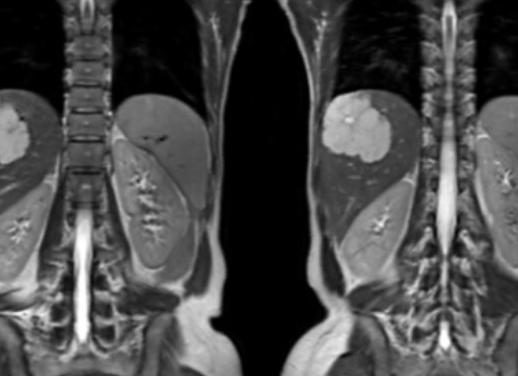

Простым и информативным способом оценки состояния ребенка в течение третьего триместра гестации, в первом (во время схваток) и втором (при потугах) периодах родов является мониторинг сердечной деятельности и сокращений матки матери. С какой недели делают КТГ? Исследование может проводиться с двадцать восьмой недели, но часто наиболее верные показатели удается получить только с тридцать второй недели. Это эффективный и безопасный метод диагностики, который не имеет противопоказаний, поэтому будущие мамы могут не волноваться ни о своем здоровье, ни о благополучии малыша.